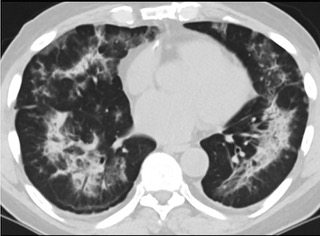

疑点一,电子烟患者的CT影像和临床表现并不具有特异性。所谓美国电子肺炎患者,其实是对没有其他合理诊断证据、吸食电子烟肺炎患者的统称。这些患者在病发前90天内吸食了电子烟,尤其值得注意的是,部分患者的CT影像特征和临床表现与病毒性肺炎患者极其相似。

疑点二,中国科研工作者从60篇研究论文中筛选出142位电子烟肺炎患者的250张影像图片,邀请3位放射科权威专家,对上述全部影像图片、相关病人临床信息以及文献原文进行了仔细全面研究与审查,又有了新的发现。

16位被文献报道为电子烟肺炎的患者被专家判定为“病毒性感染”,即有可能是新冠肺炎的“疑诊患者”,其中更有5位临床症状和治疗情况相对完整的患者被判定为“中度可疑”。因此在2019年美国报道的电子烟肺炎中存在病毒性感染的病例,而且不排除美国电子烟肺炎中存在新冠肺炎的可能性。